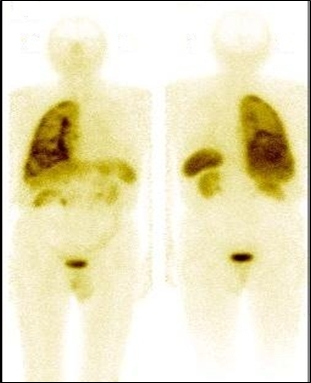

Se realizó la gammagrafía de cuerpo entero con 20 mCi (740 MBq) de octreotide marcado con 99mTc (fig. 2), obteniéndose imágenes a la 1, 4 y 24 horas post-inyección, incluyendo adquisiciones de tomografía por emisión (SPECT). La reconstrucción del estudio SPECT se llevó a cabo mediante algoritmo iterativo OSEM, con 8 subconjuntos y 4 iteraciones. El estudio demostró concentración patológica en todo el pulmón derecho; además, compromiso multifocal de hígado con incremento de su actividad en las vistas tardías.

Las vistas tomográficas reconstruidas a partir del SPECT mostraron zonas de captación del trazador en proyección de los órganos antes mencionados. Utilizando los volúmenes de la TC y el SPECT con análogos de la somatostatina y aplicando el software de fusión de imágenes (fig. 3), se obtuvo información anátomo -funcional de las lesiones descritas por separado en la tomografía y en la gammagrafía.